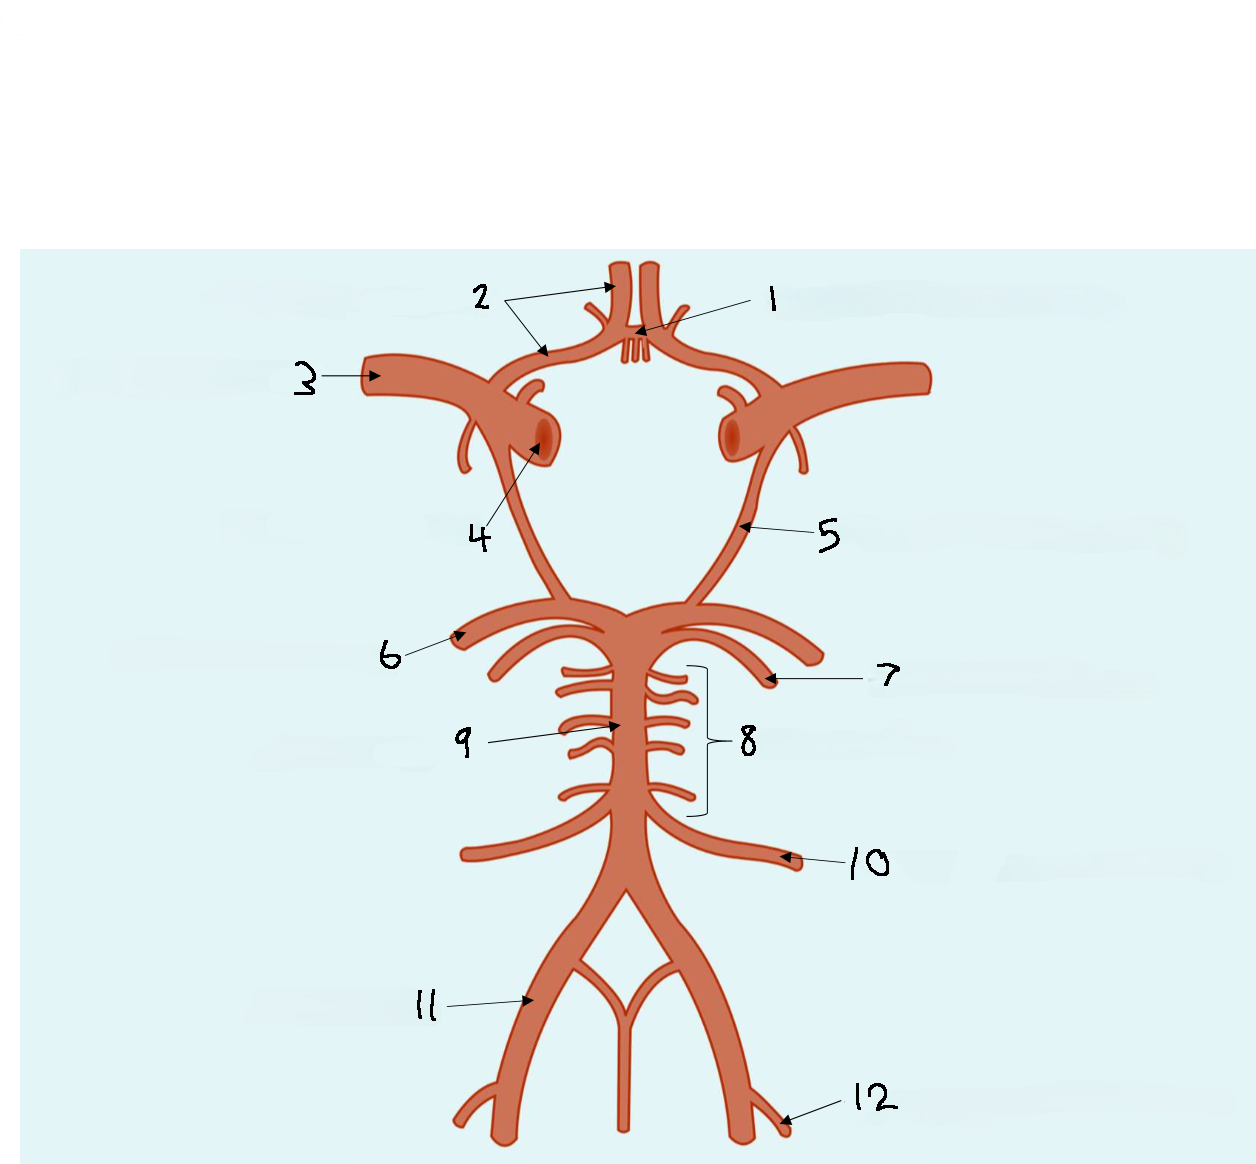

What is 1?

anterior cerebral artery

What is 2?

anterior communicating artery

What is 3?

internal carotid artery

What is 4?

middle cerebral artery

What is 5?

posterior communicating artery

What is 6?

posterior cerebral artery

What is 7?

superior cerebellar artery

What is 8?

basilar artery

What is 9?

anterior inferior cerebellar artery

What is 10?

posterior inferior cerebellar artery

What is 11?

vertebral artery